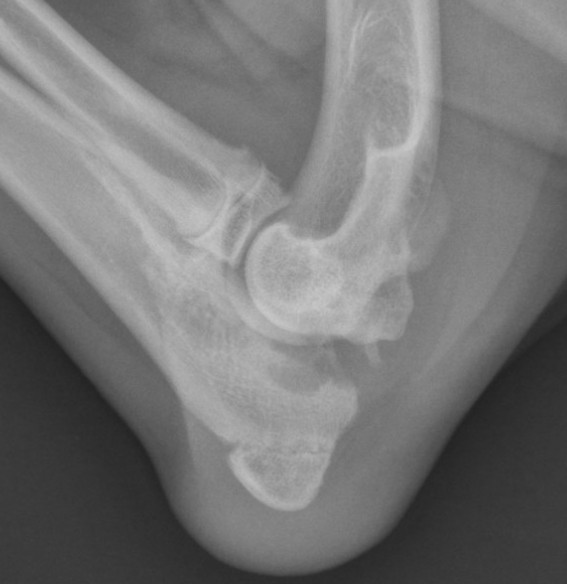

Bec de perroquet coude. De nombreuses structures anatomiques normales peuvent conduire a tort au diagnostic errone de fissures meniscales instables. La litterature anatomique decrit 4. Les osteophytes sont de deux types. Osteophytes articulaires.